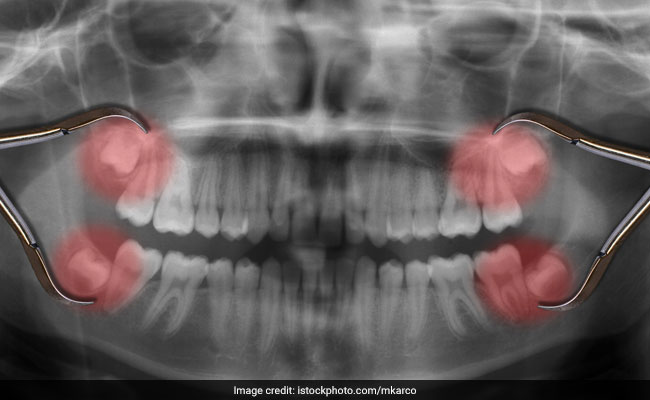

Wisdom Teeth आने पर क्यों होता है दांतों में तेज दर्द? क्या अकल दाड़ से बढ़ती है बुद्धि, जानिए क्या है इसका काम

Wisdom Teeth: अकल दाढ़ जब निकलती है तो कई लोग तेज दर्द की शिकायत भी करते हैं. ठीक तरह से अलाइन नहीं होने पर ये दूसरे दांतों को नुकसान पहुंचा सकती है जिस कारण उन्हें निकलवाना भी पड़ सकता है.